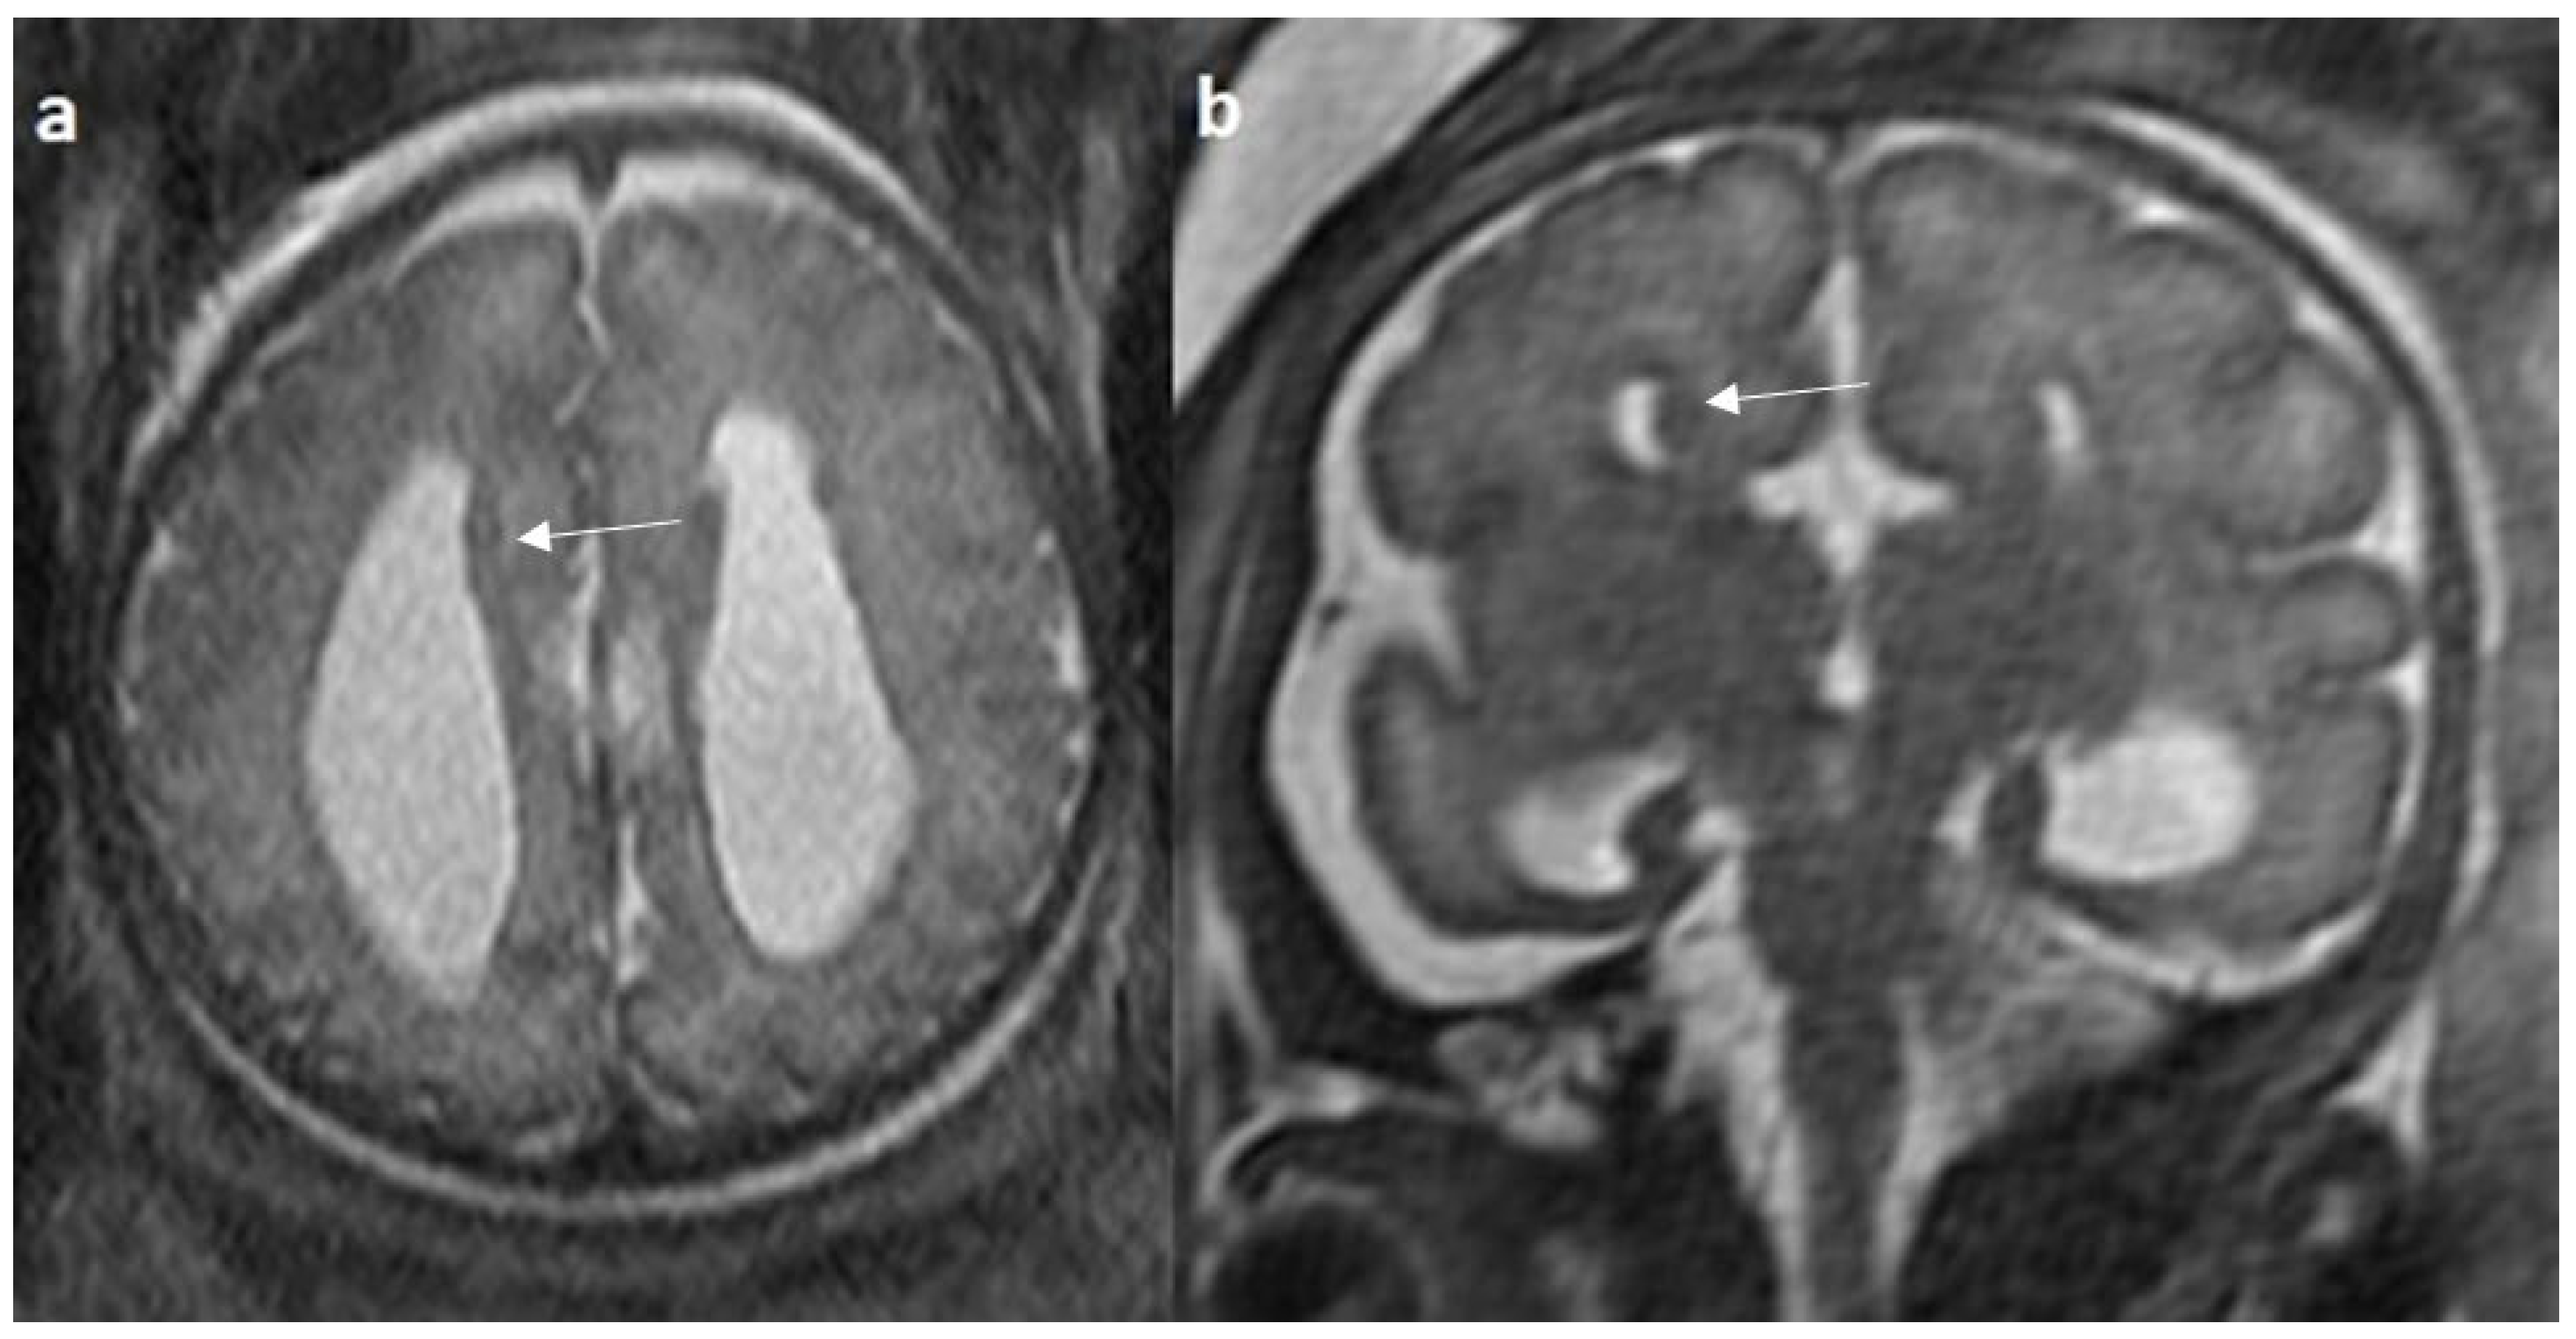

Associated CNS anomalies include 9/20 cases of interhemispheric cysts seen in 8 cases of complete agenesis and 1 case of hypoplasia. Out of 9 cases of IHC, 2 IHC were communicating with lateral ventricles. 4/20 (20%) cases had migration abnormalities such as gray matter heterotopia (Figure 8) in 3 cases of complete agenesis and hemimegalencephaly with schizencephaly in a case of dysplasia. 2 cases of cerebral cysts (2/20), including an arachnoid cyst in a case of complete agenesis class and a germinolytic cyst in a case of dysplasia. 3/20 cases of posterior fossa cysts, likely Blake’s pouch cysts, 2 in the complete agenesis class and 1 in the hypoplasia class. 2 cases of vermian hypoplasia (2/18) were noted, one each in the complete agenesis and hypoplasia classes (Figure 9 and Figure 10). A case of complete agenesis class had cerebellar hypoplasia and brain stem hypoplasia with a normal vermis. A case of complete agenesis class had a neural tube defect in the form of a sphenoidal meningoencephalocele. A case of dysplasia had diffuse thinning of white matter.

Figure 8.

Fetal MRI images of a 34 gestational weeks aged fetus, with complete agenesis of the corpus callosum and gray matter heterotopia. (a) A T2-weighted sequence image in mid sagittal plane showing complete absence of the corpus callosum with secondary changes in ventriculomegaly. (b) A T2-weighted axial sequence image showing associated subependymal heterotopia (white arrow) along the occipital horns of the bilateral lateral ventricles with moderate dilatation of lateral and third ventricles.

Figure 9.

Fetal MRI images of a 20 gestational weeks aged fetus with complete agenesis of the corpus callosum. (a) A T2-weighted sequence image in axial plane shows non-visualization of the corpus callosum, suggestive of complete agenesis. (b) A T2 weighted sequence axial image showing a well-defined extra axial fluid in the interhemispheric fissure. A lack of septum pellucidum was also observed. (c) The coronal plane shows an “steer horn” sign (arrow) in the anterior horn of the bilateral lateral ventricles and the absence of the corpus callosum and septum pellucidum in the midline region.